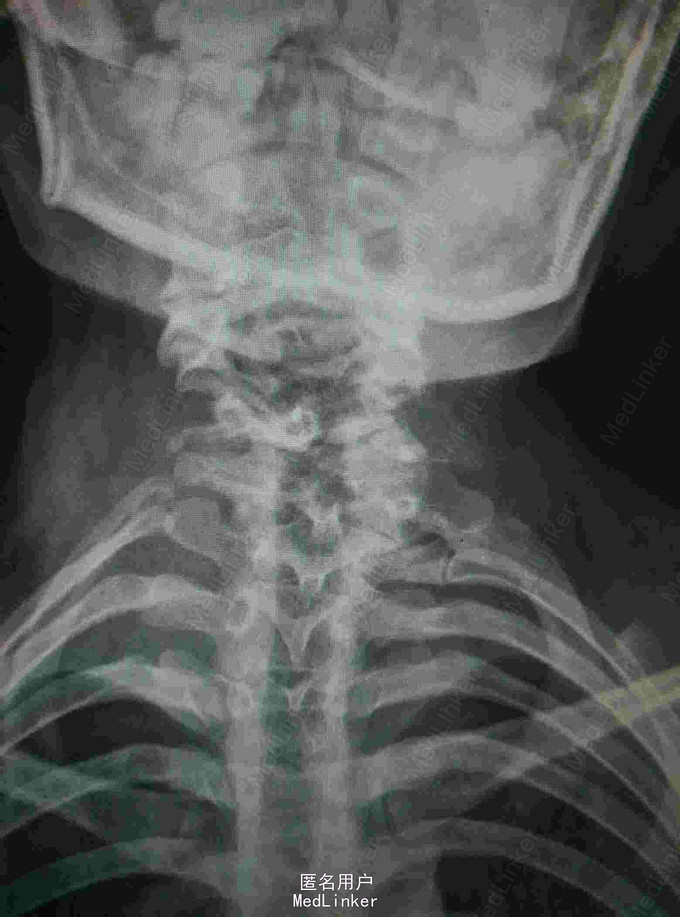

颈肩痛伴左侧肢体无力5月 患者青年男性,无明显诱因出现颈肩痛,性质钝痛,伴有左侧肢体无力,症状反复发作五月。于当地医院就诊查核磁提示颈椎结核,椎旁脓肿。患者二便正常,既往结核病史。

查体:颈椎生理弯曲消失,各棘突及椎旁压痛,胸腰椎生理弯曲不在,各棘突无压痛,椎旁无叩击痛。左侧肢体肌力降低,双侧Hoffoman征阳性,Babinski征阳性。 辅查:我院磁共振提示颈椎结核并椎旁脓肿,颈椎失稳。

诊断:颈椎结核伴椎旁脓肿 颈椎不稳 四肢不全瘫。 治疗:颈前路病灶清除植骨融合内固定术+Halos架固定,术后护肝抗结核治疗